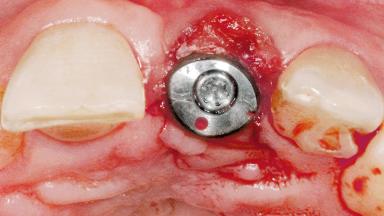

Late Flapless Placement of an Implant in a Maxillary Left Central Incisor Site

A 39-year-old male patient presented with a chief complaint of discomfort and gingival discoloration around his maxillary left central incisor. He was in good general health and was a non-smoker. His past dental history was significant because of the traumatic fracture of tooth 21 in a sporting accident at age 13. Initial dental treatment included endodontic therapy and a full-coverage restoration. The patient became symptomatic 5 years later, when structural failure of the tooth resulted in the dislodgment of the crown. Endodontic retreatment, apical surgery, and post-and-core restoration were performed.

Type of Implants One-Piece

Soft Tissue Grafting Simultaneous